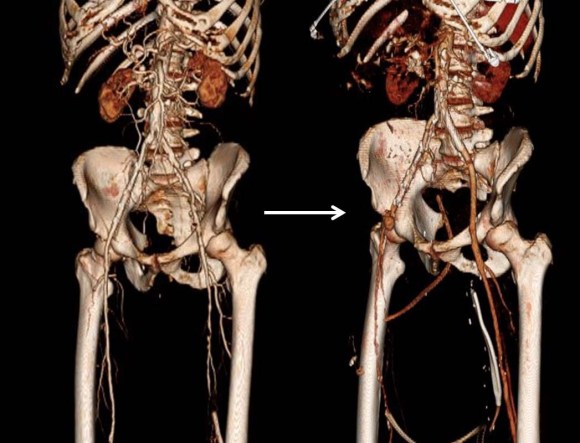

The extant arteries were smooth and plaque-free. I decided to harvest his lesser saphenous vein and through the same incision expose his distal superficial femoral artery and tibioperoneal trunk. While I anticipated some scarring, I was confident that the sections of artery I wanted to expose were easy to access because of some distance from the fused knee.

The picture shows the exposure and reversed vein graft in-situ, using the segment of lesser saphenous vein. As in prior experience in redo surgery, you can never know if a dissection will be easy or hard simply based on fear or concern for breaking something. It’s not until you start bushwacking –carving through scar and dealing with extraneous bleeding will you learn whether it was easy or hard. You can only be certain it was necessary. The only hitch was the femoral artery while well exposed, was buried in scar, and I chose not to get circumferential control as I was fairly deep, and had avid backbleeding from a posteriorly oriented collateral that required a mass clamp of the deep tissues.

Will this work better? Don’t know but it has a good chance, and I think a better chance. It is a large vein oriented in a straight path over a short distance going from good artery to good artery. This is better theoretically than a long meandering bypass with smaller vein.